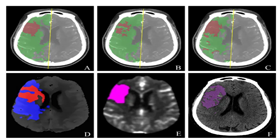

团队绝大多数都是数学专业毕业的,拥有20余年的原创性算法设计和开发经验,所有算法都已应用于大中型企业,一些算法填补了业界空白。在算法方面为软件企业和需求方提供基于具体场景的算法设计和开发服务,包括但不限于视觉识别方面的人工智能算法。